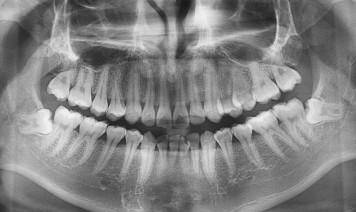

天津种植牙医院海德堡口腔告诉你哪些智齿需要拔除

长智齿的时候,我们多少会觉得很痛。有的人忍受不了这般疼痛,想拔牙一拔了之。天津海德堡口腔专家表示,虽然智齿用处不大,然而进行拔除也不必力度过硬,因为不是所有的智齿都应该拔掉的,那么,哪些牙齿才需要拔除呢?  需要拔掉的智齿有:

第一、蛀牙,如果智齿发生蛀牙,除了很简单的咬合面不深的蛀牙可以补之外,那些邻接面蛀牙,以及蛀得很深,甚至需要根管治疗的,建议拔除,杜绝后患。

第二、还有一种就智齿阻生,现实也证明,智齿阻生是智齿拔牙最常见的类型。智齿阻生指的是:智齿长不出來,残余的牙胚有可能会变性而形成口腔肿瘤。

海德堡口腔医院专家指出,阻生齿可能成为某些原因不明疼痛的病灶,异位或萌出不全的智齿亦往往会对正常咬合造成干扰,牵动下颌骨之肌肉必须常常作出异常收缩来避开这一干扰,智齿牙痛就由此而来。